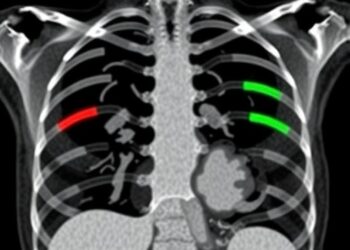

Deep Learning Detects Rib Fractures in Postmortem CT

In a groundbreaking advancement at the intersection of forensic science and artificial intelligence, researchers have unveiled an innovative deep learning ...